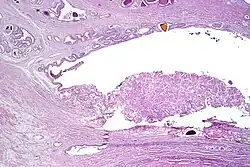

Intraductal carcinoma

Intraductal carcinoma of the prostate gland (IDCP), which is now categorised as a distinct entity by WHO 2016, includes two biologically distinct diseases. IDCP associated with invasive carcinoma (IDCP-inv) generally represents a growth pattern of invasive prostatic adenocarcinoma while the rarely encountered pure IDCP is a precursor of prostate cancer.[20] The diagnostic criterion of nuclear size at least 6 times normal is ambiguous as size could refer to either nuclear area or diameter. If area, then this criterion could be re-defined as nuclear diameter at least three times normal as it is difficult to visually compare area of nuclei.[20] It is also unclear whether IDCP could also include tumors with ductal morphology.[20] There is no consensus whether pure IDCP in needle biopsies should be managed with re-biopsy or radical therapy. A pragmatic approach would be to recommend radical therapy only for extensive pure IDCP that is morphologically unequivocal for high-grade prostate cancer.[20] Active surveillance is not appropriate when low-grade invasive cancer is associated with IDCP, as such patients usually have unsampled high-grade prostatic adenocarcinoma.[20] It is generally recommended that IDCP component of IDCP-inv should be included in tumor extent but not grade.[20] However, there are good arguments in favor of grading IDCP associated with invasive cancer.[20] WHO 2016 recommends that IDCP should not be graded, but it is unclear whether this applies to both pure IDCP and IDCP-inv.[20]

-

Intraductal carcinoma of the prostate with an infiltrative growth pattern may be morphologically difficult to distinguish from invasive cancer. One focus shows comedonecrosis (arrow), morphologically suggesting Gleason pattern 5 invasive carcinoma (a haematoxylin and eosin, b CK5/6)[20] -

Intraductal carcinoma of the prostate with very patchy basal cells identified by immunohistochemistry. At least some of the glands lacking basal cell immunoreactivity represent intraductal rather than invasive carcinoma (a haematoxylin and eosin, b CK 5/6)[20]